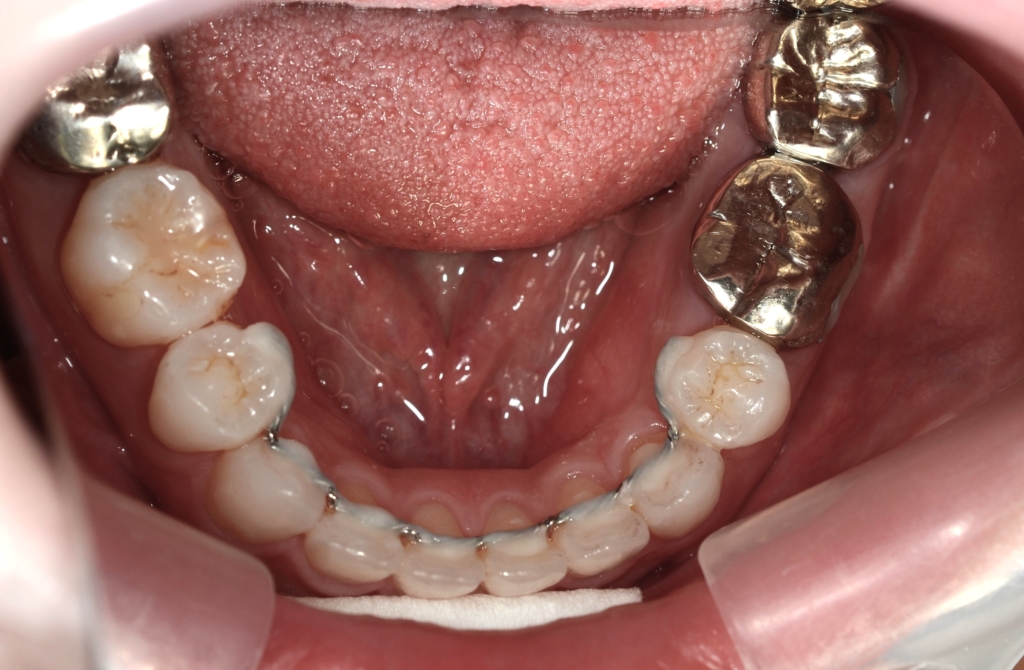

前歯部の噛み合わせに目途が付いた時点で、下の歯にも装置を付けて、合わせて治療を進めます。

噛み合わせがしっかりしたところで、上下とも第一小臼歯を抜歯して前歯を後方へ最大限に引っ込めて行きます。

【保定】 上下ともフィックスタイプ&クリアリテーナー

・スタンダードタイプのマルチブラケットシステム

・アンカースクリューを計6本

・PLAS&パラタルバーを使用 【抜歯】

上下の左右の奥歯を1本ずつの計4本(全て第一小臼歯)を抜歯